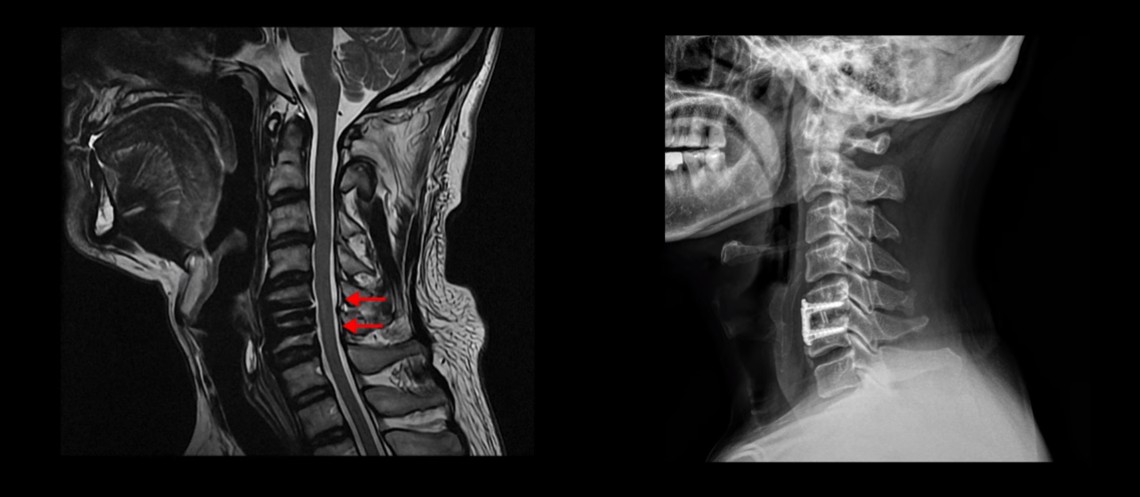

MRI를 보시면 목 5번 6번 마디에 나사가 박힌 유합술이 되어있습니다.

제자리에 나사가 잘 박혀 있고 유합술은 크게 문제가 없는 것으로 보입니다.

이 환자분의 증상인 목, 어깨, 등 통증, 두통, 어지럼증, 눈 불편함, 시력 저하 이런 증상들은 원래가 목 근육 문제와 매우 밀접하게 관련된 증상들입니다. 저희가 목디스크, 목협착 환자의 99%는 거북목 환자라고 말씀드렸습니다. 이런 증상들은 거북목과 매우 밀접한 관련이 있습니다.

이분도 X-ray를 보면 완전한 일자목, 거북목 환자입니다.